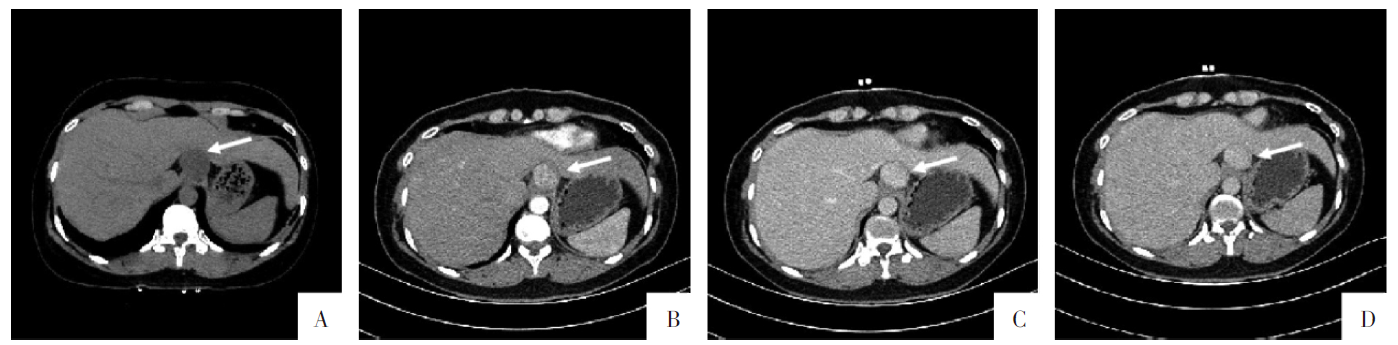

图3

病人女,34岁,腹腔恶性软组织PEComa,伴

TFE3

重排。A—D图依次为CT平扫、增强动脉期、静脉期及延迟期影像。肝胃间隙见一大小约2.9 cm×2.4 cm×3.7 cm的稍低密度结节影,CT值为17~27 HU,动脉期明显强化,CT值为69~91 HU,静脉期CT值为99~135 HU,延迟期CT值为90~105 HU。